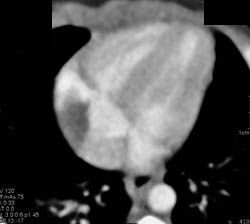

Diagnosis

Enlarged Right Atrium and Pe